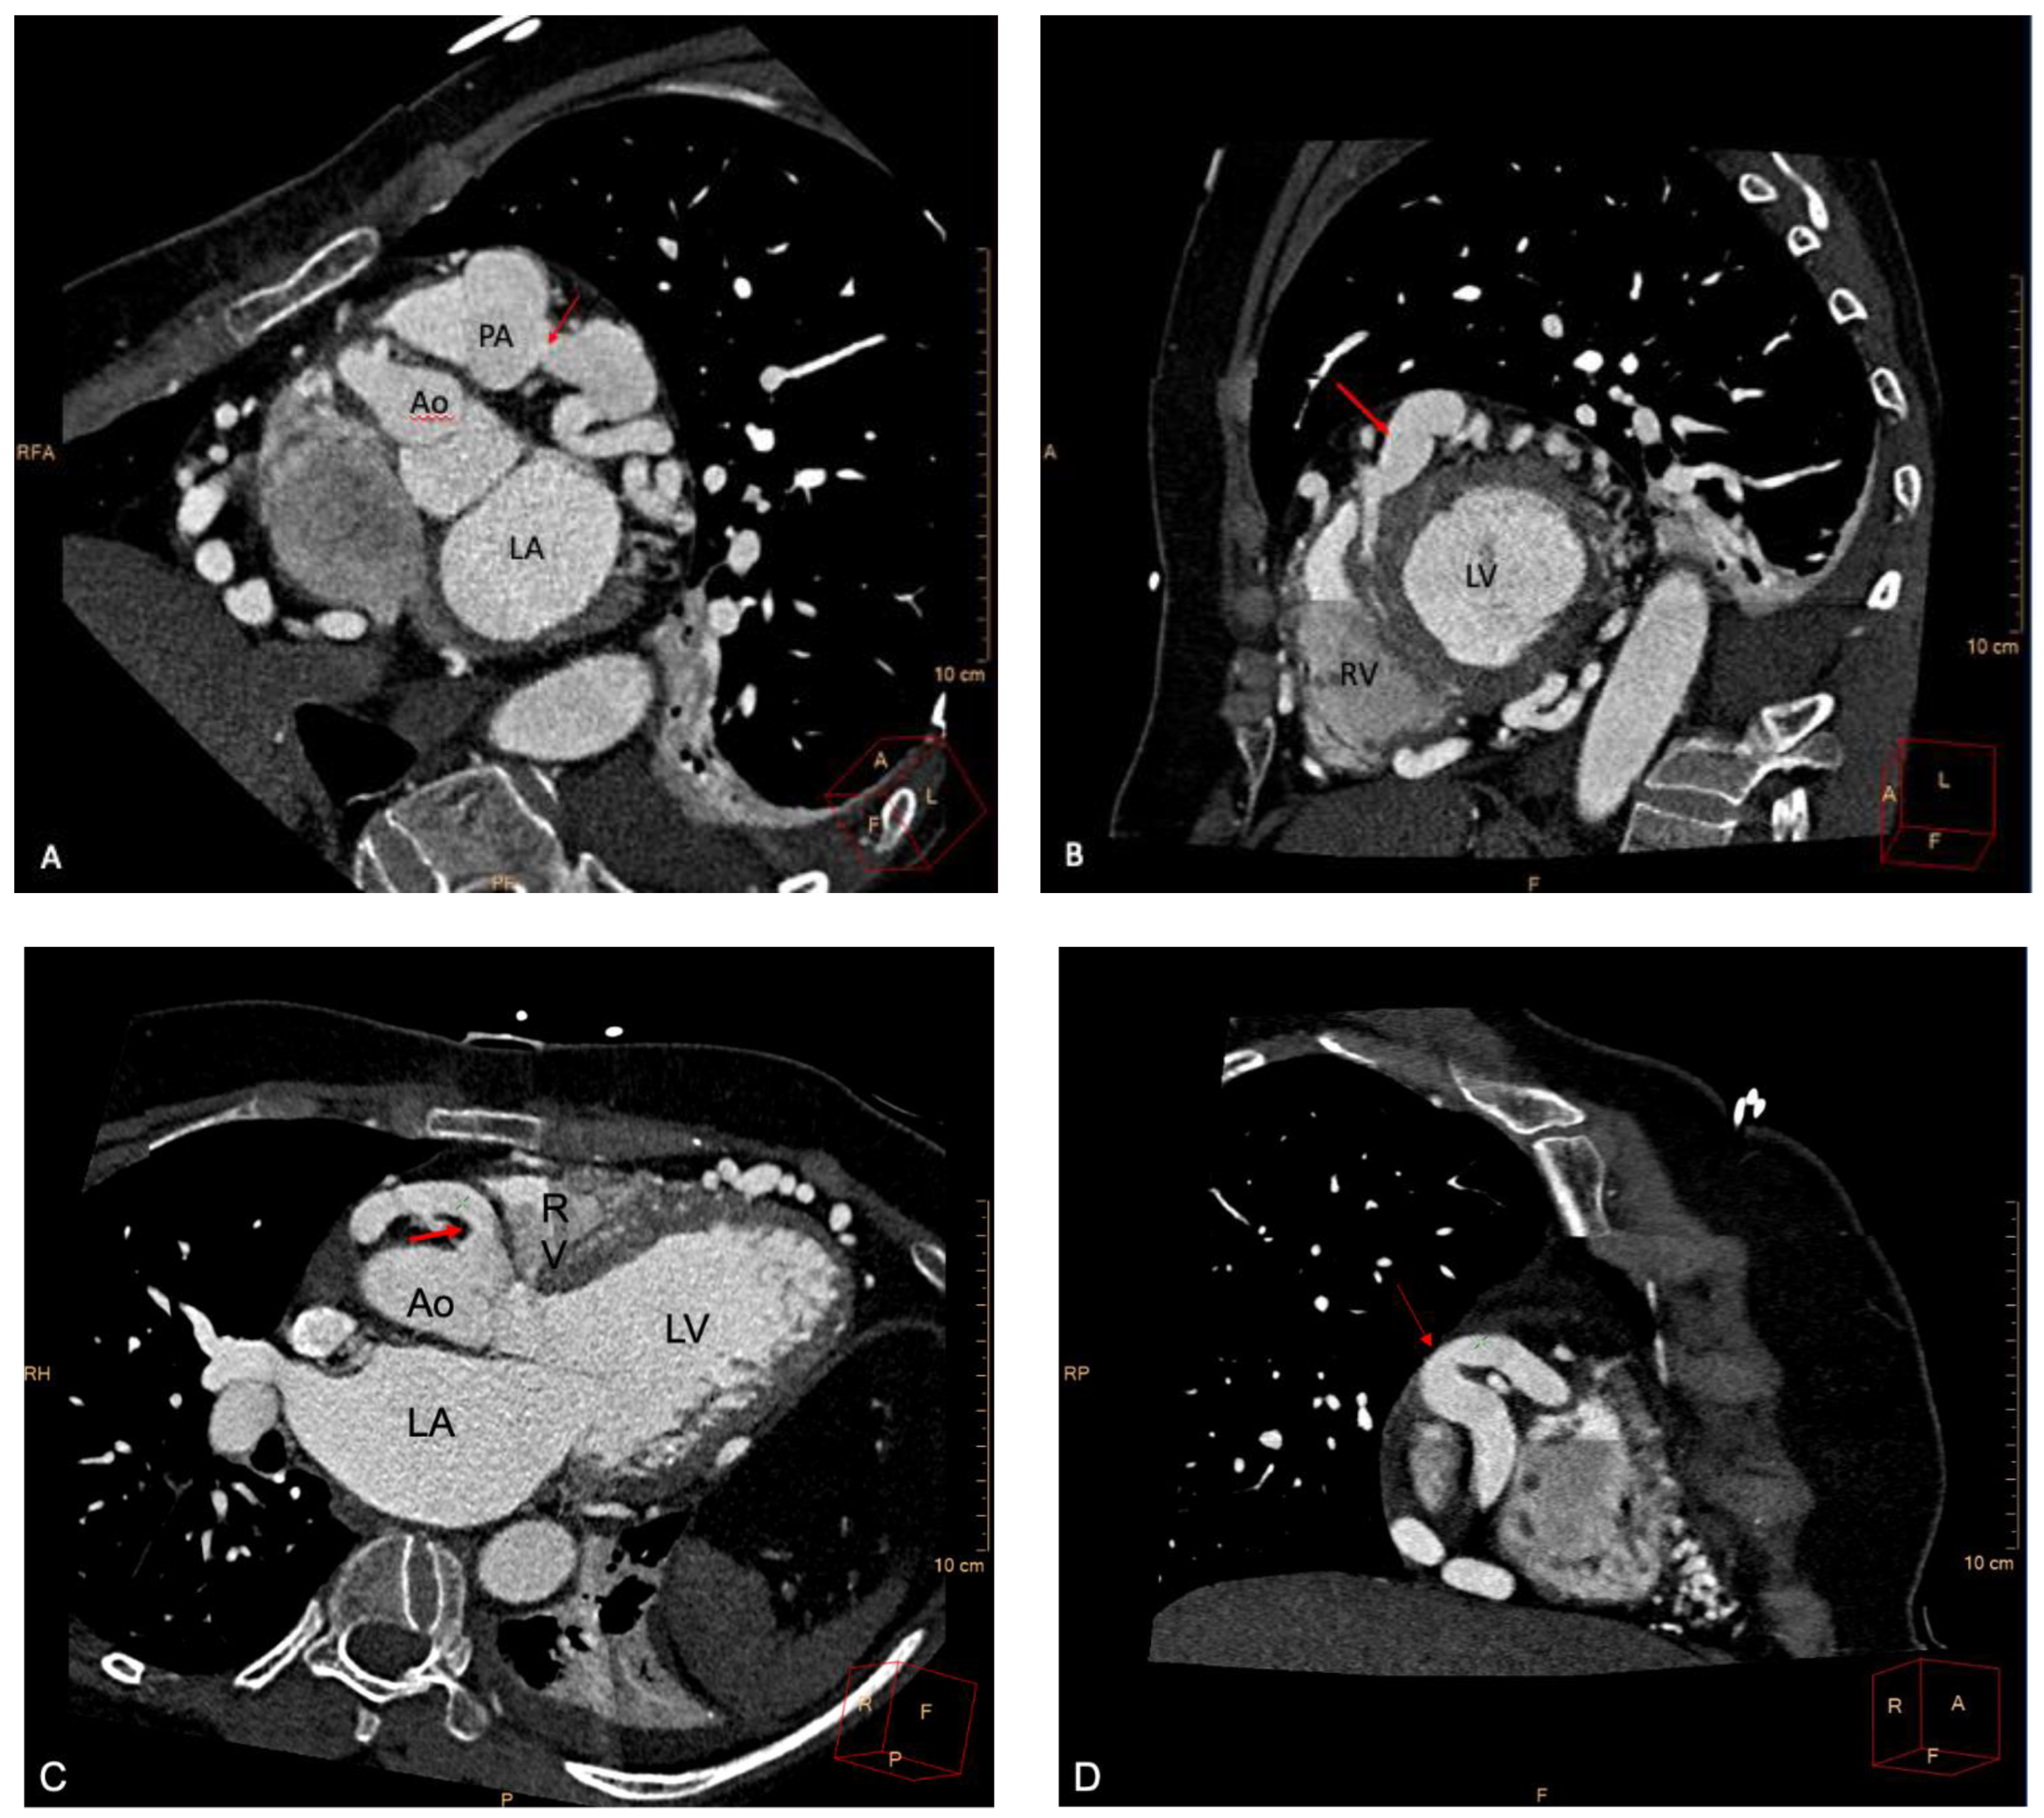

2. Case Report

Case Presentation